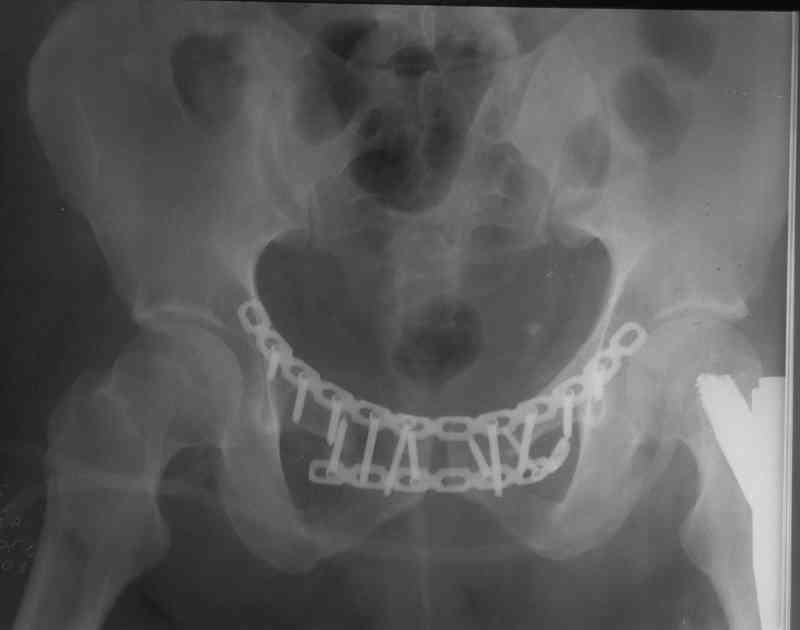

Элегантная фиксация, поздравляю.Но ваш случай : одноплоскостная горизонтальная нестабильность Tyle B2.2 отличен от представленного мной - у

моего больного + вертикальная нестабильность за счет повреждения правого крестцово-подвздошного сочленения и перелома заднего отдела подвздошной

кости- С2 тип. Поэтому и возникла дилемма : выбор оптимальной фиксации заднего отдела:

каннюлированные винты? Передняя фиксация пластиной КП ? Tension Band Plating

КП с обеих сторон? Что предпочтительнее в данном случае?

Пластина спереди (на лонные кости) открыто и каннюлированные винты с обеих сторон сзади - закрыто.